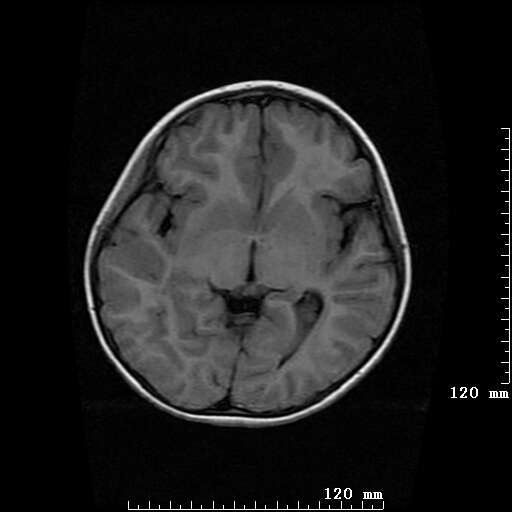

女,7岁,三岁才说话、走路。现智力尚可,走路不稳。临床怀疑大脑发育不全。

考虑 脑白质发育不良

脑折质变薄,双侧侧脑室稍扩张,支持考虑脑折质发育不良

侧脑室周围白质软化症。

考虑胼胝体发育不全,髓鞘形成不良。

支持考虑胼胝体发育不全,髓鞘形成不良。

脑裂畸形伴灰质异位

侧脑室周围白质数量减少,侧脑室不对称性扩大,左侧侧脑室后角呈方形改变,脑沟加深,结合临床考虑脑室周围白质软化症(pvl)。期待结果!

只看出灰质异位

支持脑白质发育不良。